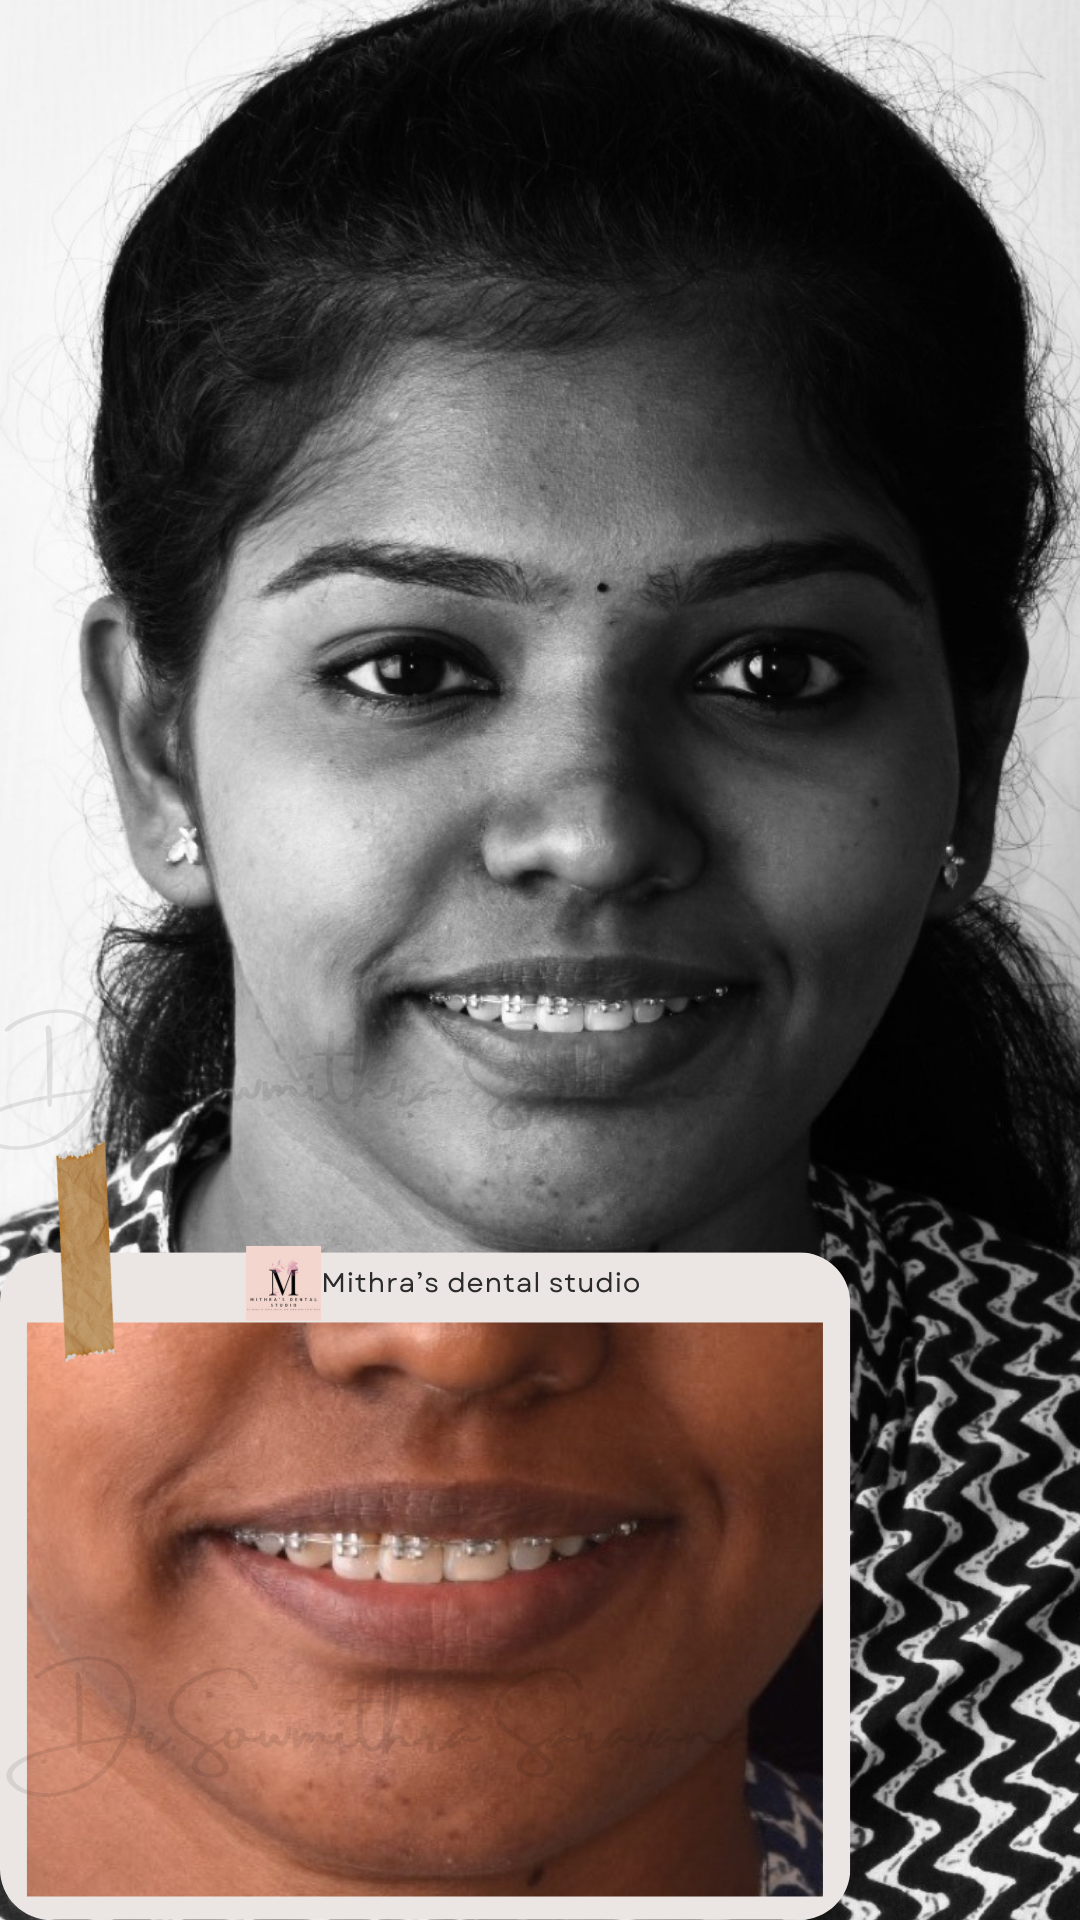

smile makeover

Smile Journey!

May be it is too simple to treat but the way this smile makeover made a difference in her life is immense! thats how wonderful smile curves are created!